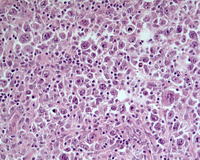

Figure 2: NLPHL areas in higher power

At high power, scattered L&H/LP ("popcorn") cells are noted amidst histiocytes and lymphocytes.